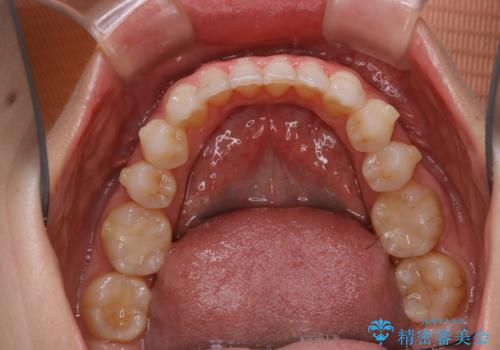

- インビザライン(マウスピース矯正)の治療中にステインが気になり、クリーニング希望とのことでした。

アタッチメントの周囲などに、ステインの付着や、プラークがみられたためPMTC(自費クリーニング)30分コースを行いました。

自費クリーニング(pmtc)30分コース¥5000+tax